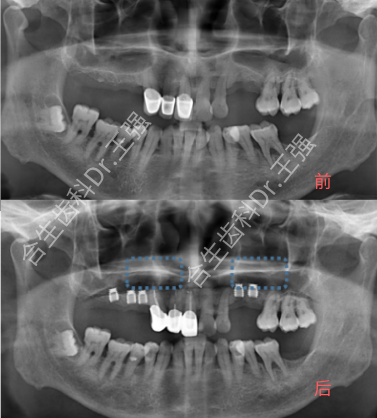

以下就是患有牙周炎、牙槽骨条件不佳、骨量不足的种植牙病例展示: